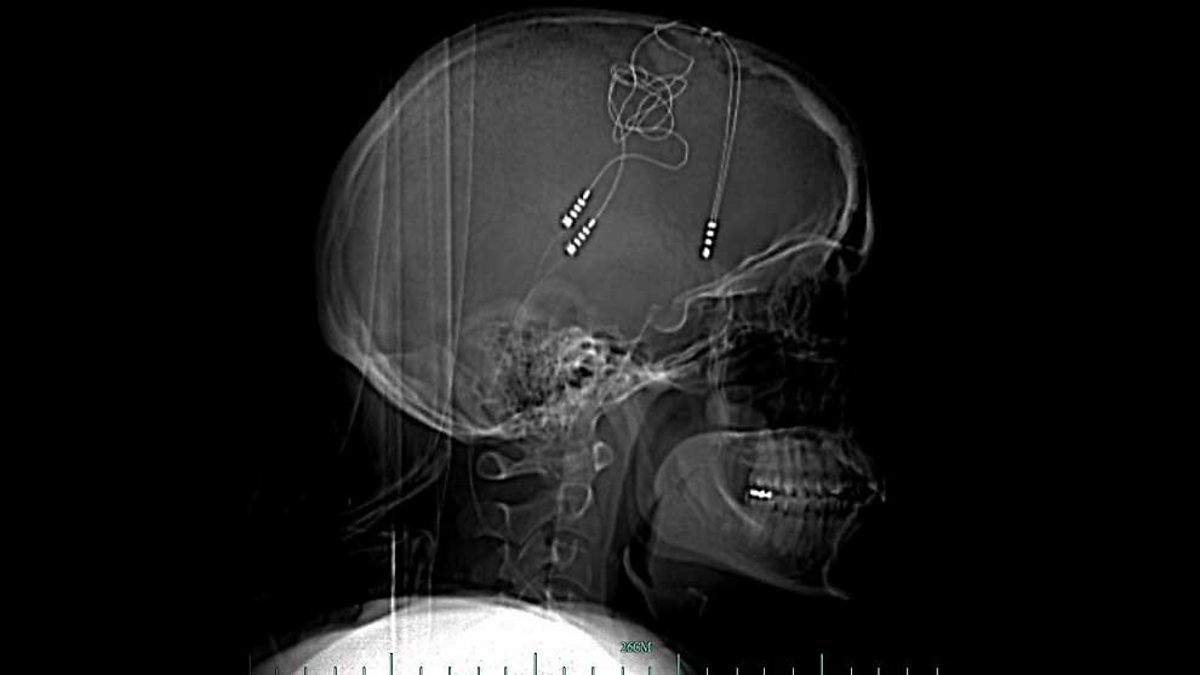

"Being a cyborg restored my humanity"

When all the other treatments failed to help her depression Brandy Ellis turned to technology. She now has electronics in her brain to regulate her emotions. She explains whether she feels more or less human as a result.